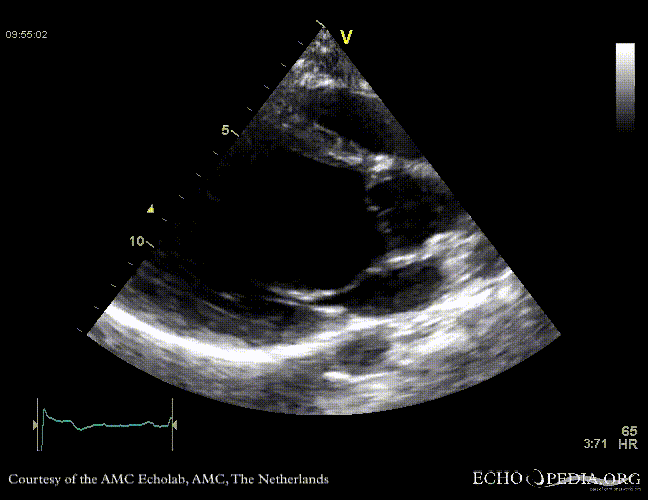

Case 10